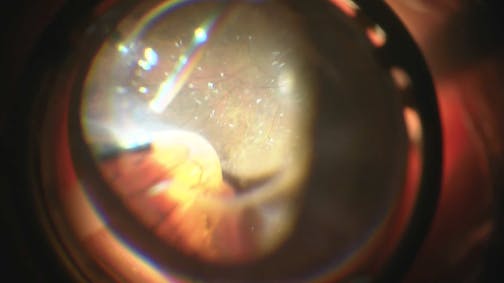

Optic Nerve Pit

Kourous A. Rezaei, MD